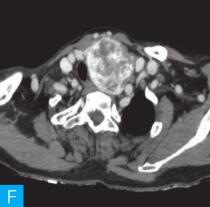

甲状腺CT检查:CT检查设备为256层iCT,病人采取仰卧位,扫描范围自外耳道平面至下颌角以下,常规扫描层厚为0.9mm、层间隔0.9mm,电压120kV,管电流280mA,矩阵512×512;经右肘静脉团注法增强扫描,碘海醇80ml,流速4ml/s,动脉期25秒扫描,静脉期60秒扫描。见图1。

图1 甲状腺CT

A、B.甲状腺CT横断面平扫;C~H.甲状腺CT横断面增强

答案A 解析:甲状腺左叶病变边界清楚,形态较规则,密度不均匀,部分为实性改变,部分为囊性灶,其内可见斑点状粗大钙化灶,气管及食管向右推移,左侧颈总动脉向左后推移,胸锁乳突肌向左前推移。根据表现病变不是单纯囊性病变。

答案C 解析:该病灶病史时间长,无发热及疼痛;病变位于一侧甲状腺,边界清楚;甲状腺血流及静态显像示:甲状腺左叶较大“凉”结节。因此不考虑恶性肿瘤及感染性病变。病变强化特点为结节状改变,呈现肿块样,故考虑肿瘤样病变。

CT平扫可见甲状腺左叶圆形以低密度为主病灶,大小为8.0cm×6.5cm,边界清晰,边缘尚光整,其内密度不均匀,低密度区CT值18HU,部分密度稍高,并可见斑点状粗大钙化影;CT增强后,甲状腺左叶病变呈不均匀渐进性强化,结节状改变,动脉期强化区CT值99HU,静脉期CT值85HU,且强化范围增大,提示该病变的血供较为丰富,应该考虑肿瘤样病变,结节性甲状腺肿可能性大。

本病例CT扫描发现起源于甲状腺较为容易,但要观察病变是囊性、实质性或囊实性及其供血,CT增强扫描十分必要,易于显示囊实性病变及其供血情况,其结节状改变更加显著,有助于判定病灶的血液供应情况。本病例基本征象为类圆形、边缘清晰、内粗大钙化、结节状强化之肿块。

该例病变位于甲状腺左叶,左叶不对称性增大,其内多发散在不规则强化结节影,斑点状粗大钙化,钙化周围可见星状伪影,提示钙化为长期慢性形成,而且钙化比较致密。肿块虽然很大,但与邻近气管、食管及血管等无明显侵犯或浸润征象。病变内部可见多发囊变区,增强检查实性部分呈明显均匀强化,包膜完整。双侧锁骨上区未见肿大淋巴结。提示病变为良性。病变多发,伴囊变、钙化,临床为中老年女性病人,颈前无痛性肿物。结节性甲状腺肿诊断明确。结节性甲状腺肿常常较大,术前影像学的评估包括:①病变的范围,累及胸骨下的范围决定手术治疗的方式,手术是否需要打开胸骨;②病变与气管的关系,是否具有气管软化,如果存在气管软化,要提醒临床医生手术过程中以及术后出现呼吸困难;③注意是否合并甲状腺癌,尤其是乳头状癌。要仔细寻找包膜是否完整,内部有无微小的乳头,以及邻近Ⅵ区或Ⅳ区是否伴有淋巴结转移。